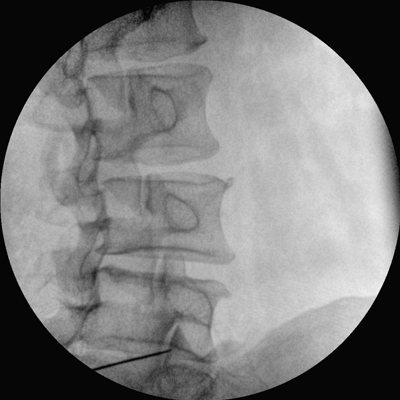

專(zhuān)業(yè)的圖像處理系統(tǒng),為您提供高分辨率、高灰階圖像。